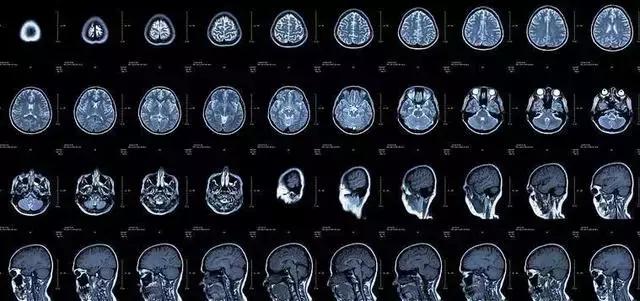

磁共振于对软组织滑膜、血管、神经、肌肉、肌腱、韧带、和透明软骨的分辨率高。由于其特殊的性质,磁共振看骨头不行,而在大脑的检查中则有着不可替代的作用。

▲MRI的脑部检查影像

在这里还要顺便提一下,磁共振扫描的时间相对CT会更长,但是并没有辐射,相对安全。还要说一句的是磁共振仪器是一个巨大的磁场,进去磁共振室一定要卸下随身携带的金属物品,不然都会被吸到机器上。